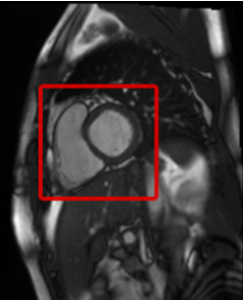

Cardiac MRI is the modality of choice in cardiology for the assessment of the ventricular function, since the heart’s anatomy is visualized with high resolution. This functional assessment is a time-consuming task for the cardiac radiologist when performed manually. Therefore, computer-driven diagnostic solutions are of particular importance for clinical applications. In order to ensure the success of such computer aided diagnosis algorithms however, a correct, initial localisation of the heart region in the raw data is crucial. For this purpose, we present a novel, simple and fully automated approach for localizing the heart region in cardiac cine MR data. Without the need for prior knowledge or training datasets, this method enables a ready to use application for a robust localization. This processing step is a fundamental component for the development of integrated automated applications.